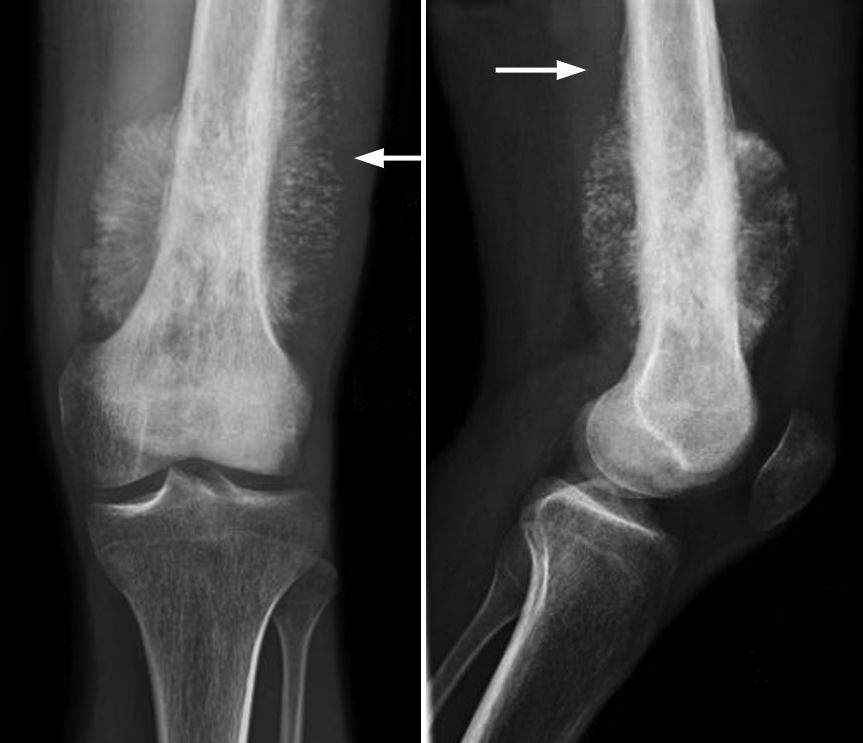

Osteosarcoma

Secondo la MU l'Osteosarcoma, o sarcoma osteogenico, è il più comune e il più maligno dei tumori ossei. Colpisce prevalentemente i bambini in età prepuberale e gli adolescenti e la sede prevalente è l'estremità di ossa lunghe, come femore e tibia, ma anche omero.